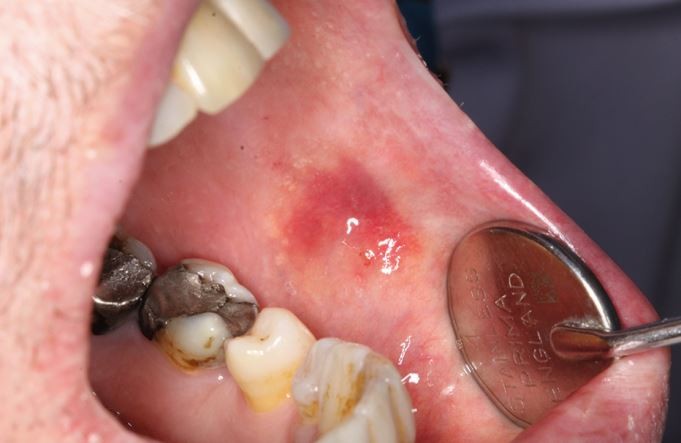

Bruxism was defined in 2013 as 'repetitive jaw-muscle activity characterised by clenching or grinding of the teeth and/or by bracing or thrusting of the mandible' by international concensus,1 with supplemental classification of sleep or awake bruxism. It has also been classified as a sleep movement disorder.2,3 Tooth surface loss (TSL) is a well-recognised phenomenon, evident in all age groups, with well-defined management strategies.4,5,6,7 TSL is multifactorial in nature but one aspect leading to TSL is parafunctional behaviours of the oral and perioral tissues, in particular, bruxism. Damage from bruxism can be minor or substantial, affecting hard tissues, with attrition of occlusal surfaces of the teeth, fractures of teeth or restorations (Fig. 1), including implant retained restorations (Fig. 2) and can lead to damage or changes in the soft tissues via soft tissue trauma (Fig. 3), ulceration, hypertrophy or hyperplasia (Fig. 4). There have even been reports of parotid duct obstruction with consequent symptoms.8,9 Function may be impacted and aesthetics changed, leading to negative psychological impact and in some, social isolation and poor quality of life.10,11,12 Persistent increased muscular activity may become symptomatic, with facial pain and aspects of temporomandibular symptoms, but also may be symptomless. The impact of the activity can damage tissues that may then become painful, for example with a fracture of a tooth, but often with no apparent pre-existing history of bruxism. Control of bruxism and other parafunctional activity and the damage that these can produce may significantly improve function and quality of life, but in addition, may also improve outcomes for patients with reduced clinical time and reduced financial burden, to both the patient and the health service. A primary issue with bruxists is predicting the long-term outcomes. While many will not require active intervention, others do require methods of protection of the dentition and tissues. Risk assessments for prescribing are difficult and rely on historical evidence of tissue damage and ongoing behaviour patterns, with real-time predictors of future risks.

When considering the impact of bruxism, whether awake or asleep, both hard and soft tissues should be considered. While extreme attrition of the dentition is very clear, changes within soft tissues may be more subtle. However, most changes are relatively easy to identify and flag during routine examination and a detailed examination may then be instigated to assess the risk posed to the patient's oral health. Issues to review are shown in Table 2.